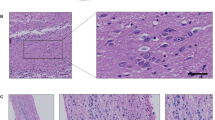

The double immunostaining of oligomeric α-syn and OMP showed a similar immunofluorescence signal in patients and controls (Fig. 1A), as further confirmed by immunofluorescence analysis (RGB pixels analysis): OD patients (n = 10, 2.8 ± 0.51) versus CTRLs (n = 10, 3.3 ± 0.85) (Fig. 1B).

Neurodegeneration-associated marker expression levels. Representative immunofluorescent images showing the expression pattern of oligomeric α-syn (green) (A), tau protein (green) (C) and Aβ (green) (E) in ONs from healthy controls (CTRL) and post-COVID-19 OD patients. Nuclei were stained with DAPI (blue). Scale bar, 10 µm. Graphs showing immunofluorescence signal quantification of oligomeric α-syn (B), tau protein (D), and Aβ (F) in each group evaluated by ImageJ software. Data points represent the mean value ± SEM

As well, the double immunofluorescence staining of tau with OMP and Aβ with β3-tub excluded significant differences between patients and controls (Fig. 1C, E), as demonstrated by RGB immunofluorescence analysis: Tau, OD (n = 10, 2.2 ± 0.46) versus CTRLs (n = 9, 1.8 ± 0.56; Aβ, OD (n = 10, 2.3 ± 0.41) versus CTRLs (n = 8, 1.9 ± 0.49) (Fig. 1D, F). The immunofluorescence expression patterns observed for tau and Aβ were consistent with previous data reported by Brozzetti and colleagues [10]. Tau positivity presented a homogenous intracytoplasmic distribution, while Aβ positivity showed a dot-like positivity, distributed in the proximity of the nucleus.